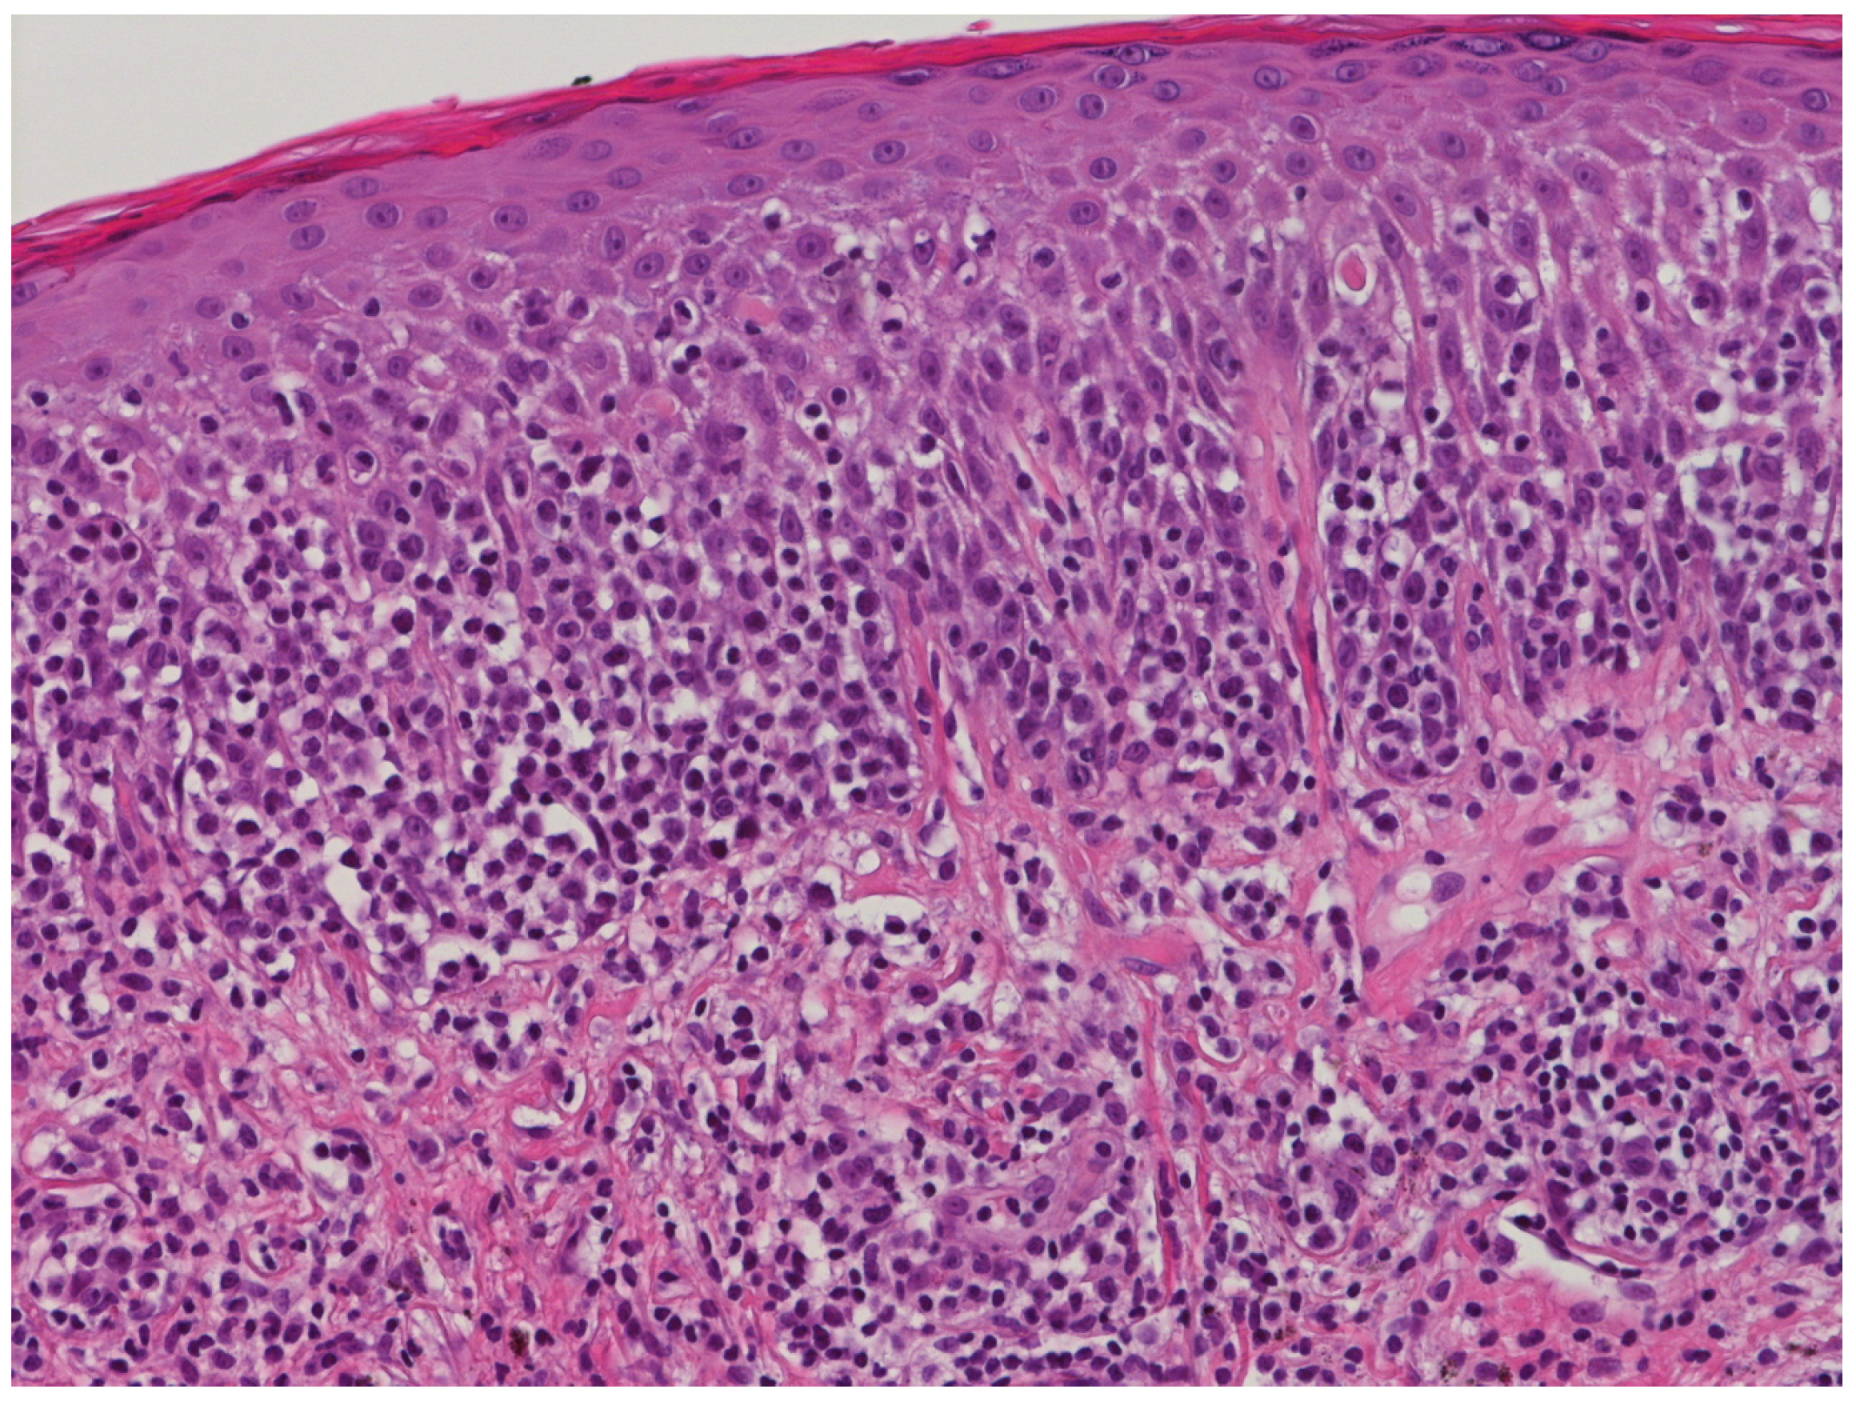

2. Case Presentation